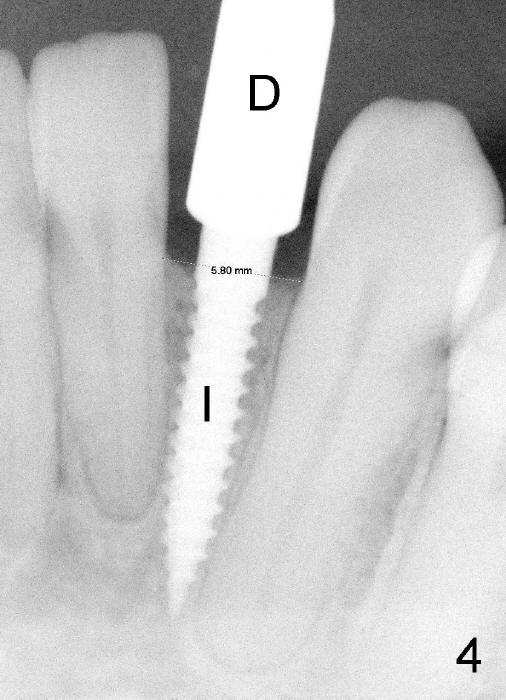

Informed consent is obtained with emphasis of potential damage to the neighboring roots. Two PAs have to be taken with the first pilot drill (1.5 mm) in place for determination of initial trajectory (Fig.2,3). Osteotomy is enlarged coronally with 2 mm pilot drill. Finally a 3x17 mm one piece implant is placed with primary stability, determined tactilely (Fig.4). Immediate provisional is fabricated. To avoid micromovement, the immediate provisional (Fig.5 P) is bonded to the neighboring teeth with composite (*); it is further fixed in place with a lingual retainer (Fig.6 arrowhead).